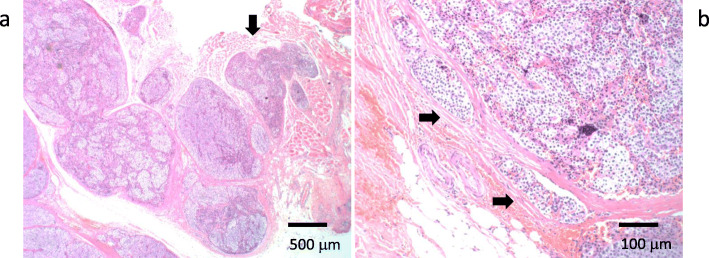

Fig. 6.

Histological findings of the recurrent tumor right next to the trachea (hematoxylin and eosin stain). a The tumor invaded through the muscle (arrow). b The tumor invaded the vessels (arrows)